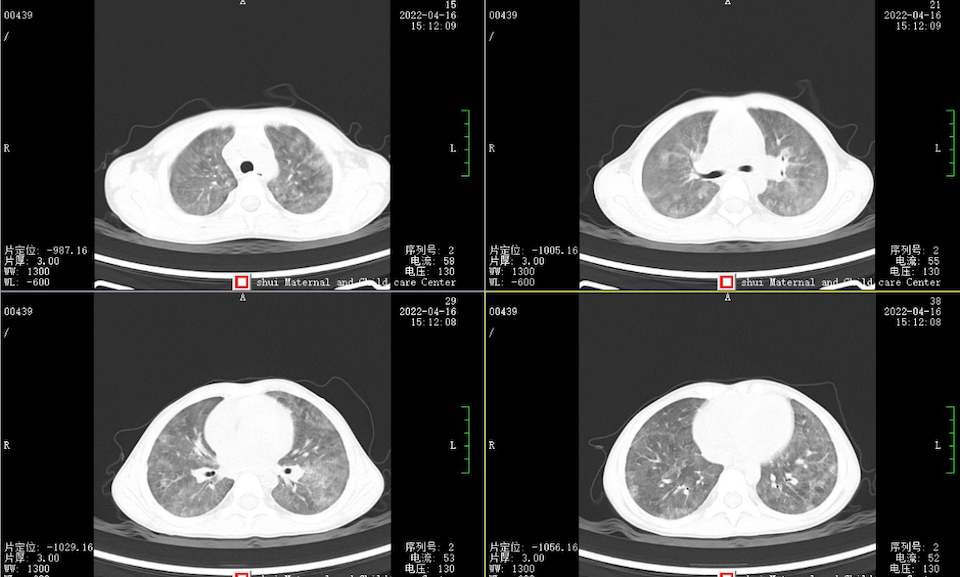

2022年,本科接诊了一位反复贫血3年的患儿。在这漫长的三年里,患儿曾辗转多家三甲医院门诊及住院治疗,均因“急性支气管炎、缺铁性贫血”予抗感染、止咳化痰、输血、补铁等治疗,病情虽一度好转,但贫血症状始终反复出现。在我科住院治疗期间,经过抗感染、补铁等综合治疗,患儿无发热,咳嗽症状也有所改善。然而,复查血红蛋白的结果却显示进一步下降,这引发了我们的高度警觉。胸部CT检查结果提示两肺各叶见广泛模糊及磨玻璃样影,这一异常征象为我们提供了进一步探索疾病真相的线索。

图1 :两肺见广泛模糊及磨玻璃样影